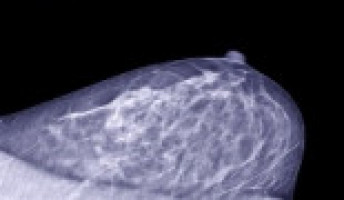

The pilot study, published in the Annals of Family Medicine, examined the feasibility of performing mammograms in women insured by Medicaid or both Medicaid and Medicare (dual-eligible patients) while they were hospitalised.

Of the 21 women who were identified as appropriate candidates for an inpatient mammogram, 17 women, who were an average age of 59, successfully completed the mammogram. The other four patients were discharged from the hospital before the mammograms could be coordinated.

Of the 17 women who completed an inpatient mammogram, 35% had never had a mammogram and the other women were overdue for their mammograms by four years on average.

All the mammograms were negative, except one, which was inconclusive, and additional imaging evaluation was recommended to rule out cancer. Completing a mammogram did not increase the patients' hospital length of stay.